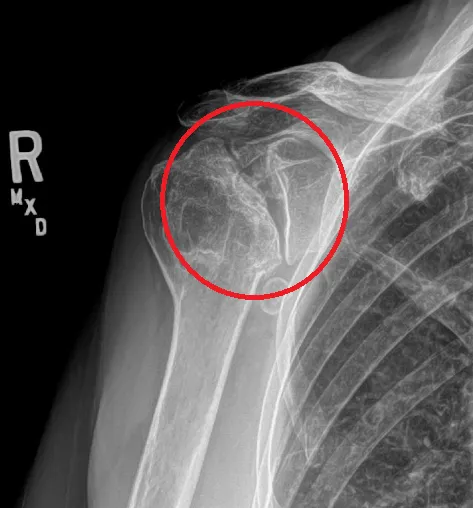

肩關節退化 由肩胛骨與鎖骨、肱骨所組成的肩關節之銜接處沒有達到正確的排列位置,進而導致此關節所負責之動作方向長年導致磨損或增生骨刺逐漸產生角度產生受限、週邊肌肉神經筋膜等軟組織產生發炎、鈣化、不適症狀,即為肩關節退化。

肩關節退化 的診斷方式有哪些?

X光檢查以及常見該肌肉力量、動作功能、症狀主述判斷